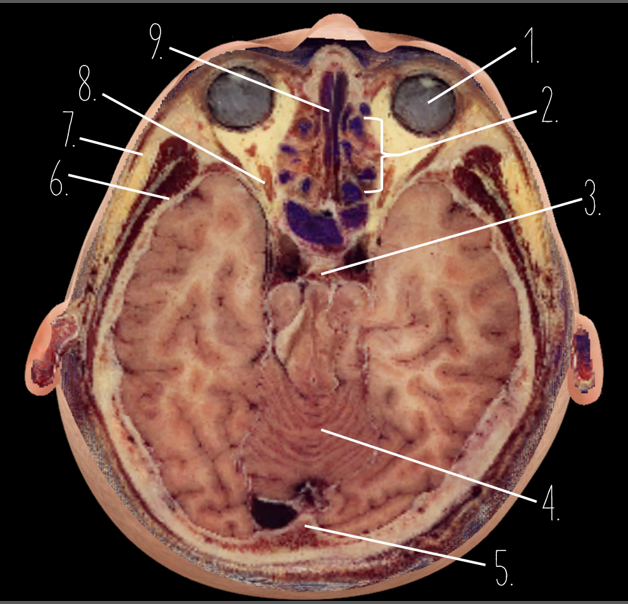

1?

Nasal Bone

2?

Maxillary Sinus

3?

External Acoustic Meatus

4?

Pons

5?

Cerebellum

6?

Mastoid Air Cells

7?

Mandibular Condyles

8?

Sphenoid Bone

9?

Maxillary Bone